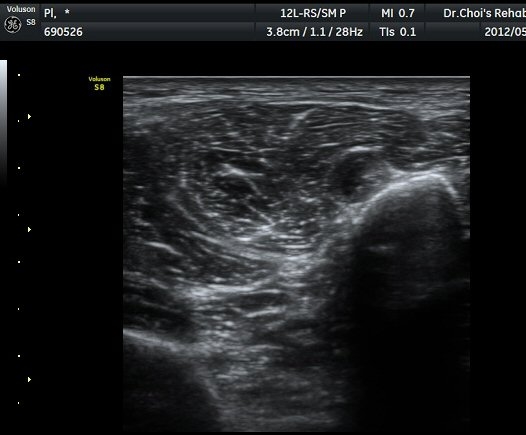

ŽÃËÀÚ¸¦ Á¶±Ý ´õ ¾Æ·¡·Î À̵¿ÇÏ´Ï ºñ°ñÀÇ ¾ÕÂÊ¿¡¼­ ÃѺñ°ñ½Å°æ õºñ°ñ½Å°æ°ú ½Éºñ°ñ½Å°æÀ¸·Î ³ª´©¾îÁø´Ù(±×¸² 6).